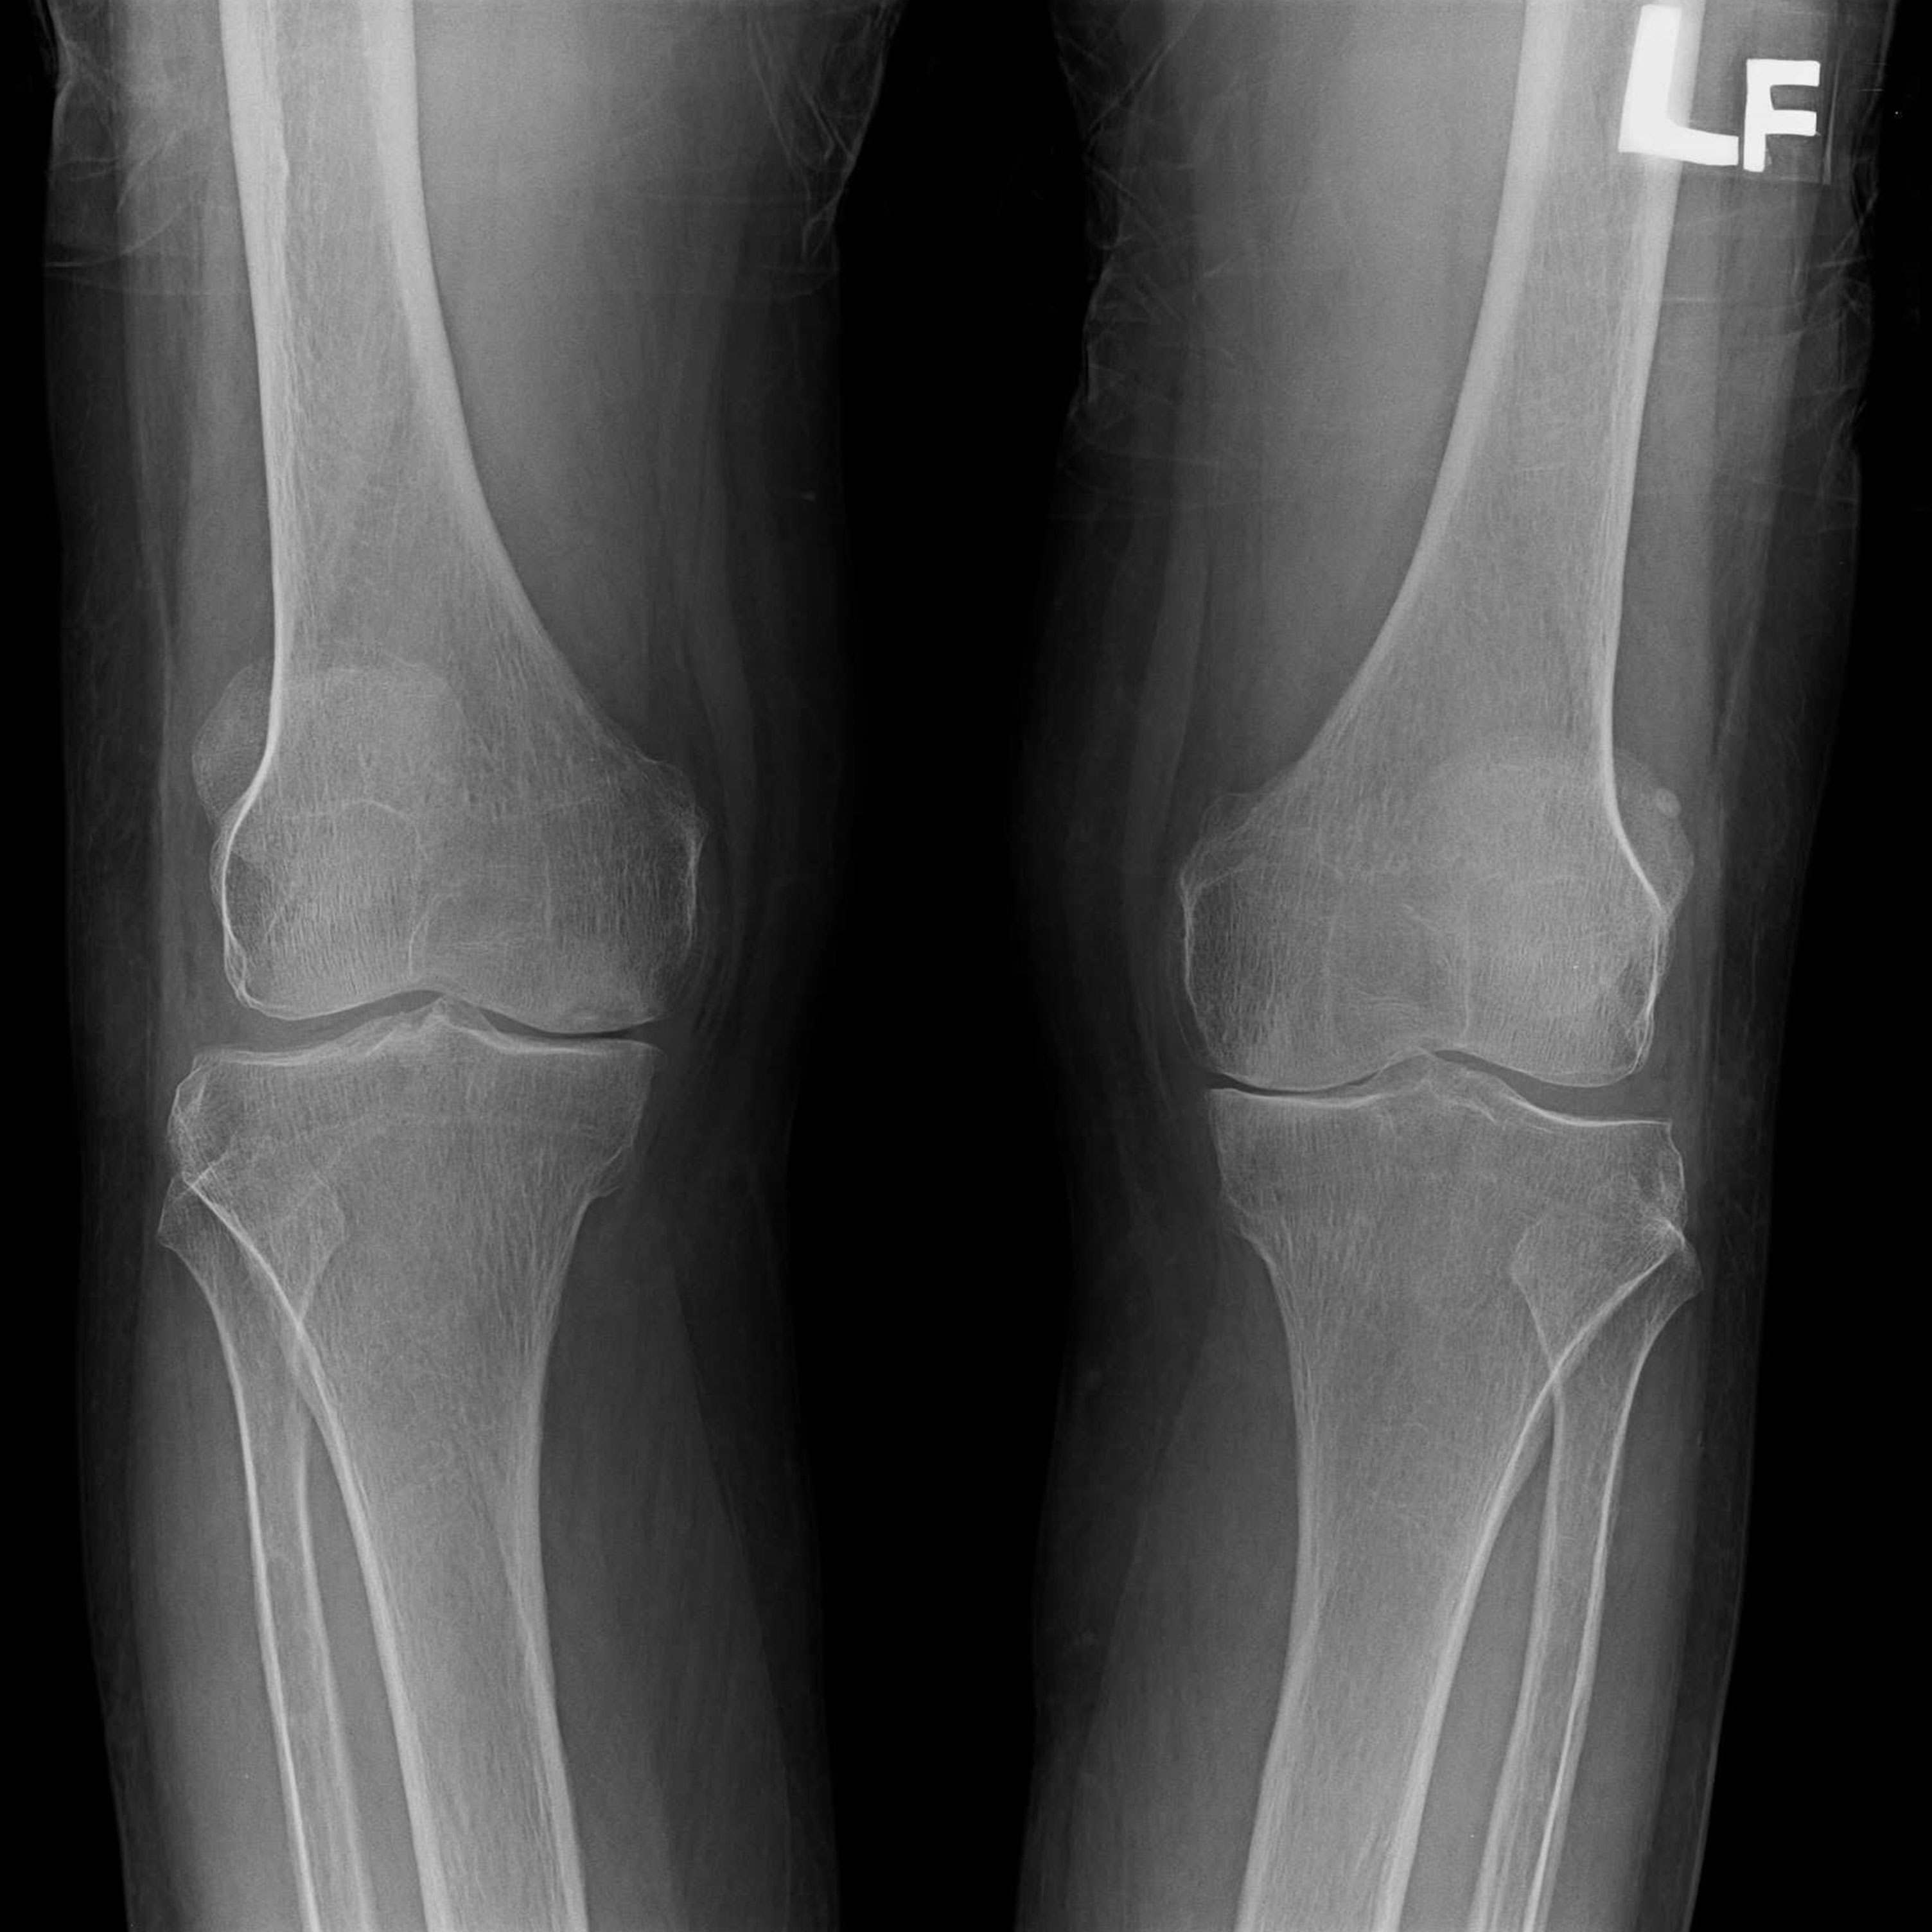

傳統部分膝置換 首頁 案例分享 膝關節手術 傳統部分膝置換 殷女士 65歲 術前 術後 張女士 71歲 術前 術後 蔡女士 74歲 術前 術後 張女士71歲 術前 術後 翁女士70歲 術前 術後 劉女士 80歲 術前 術後